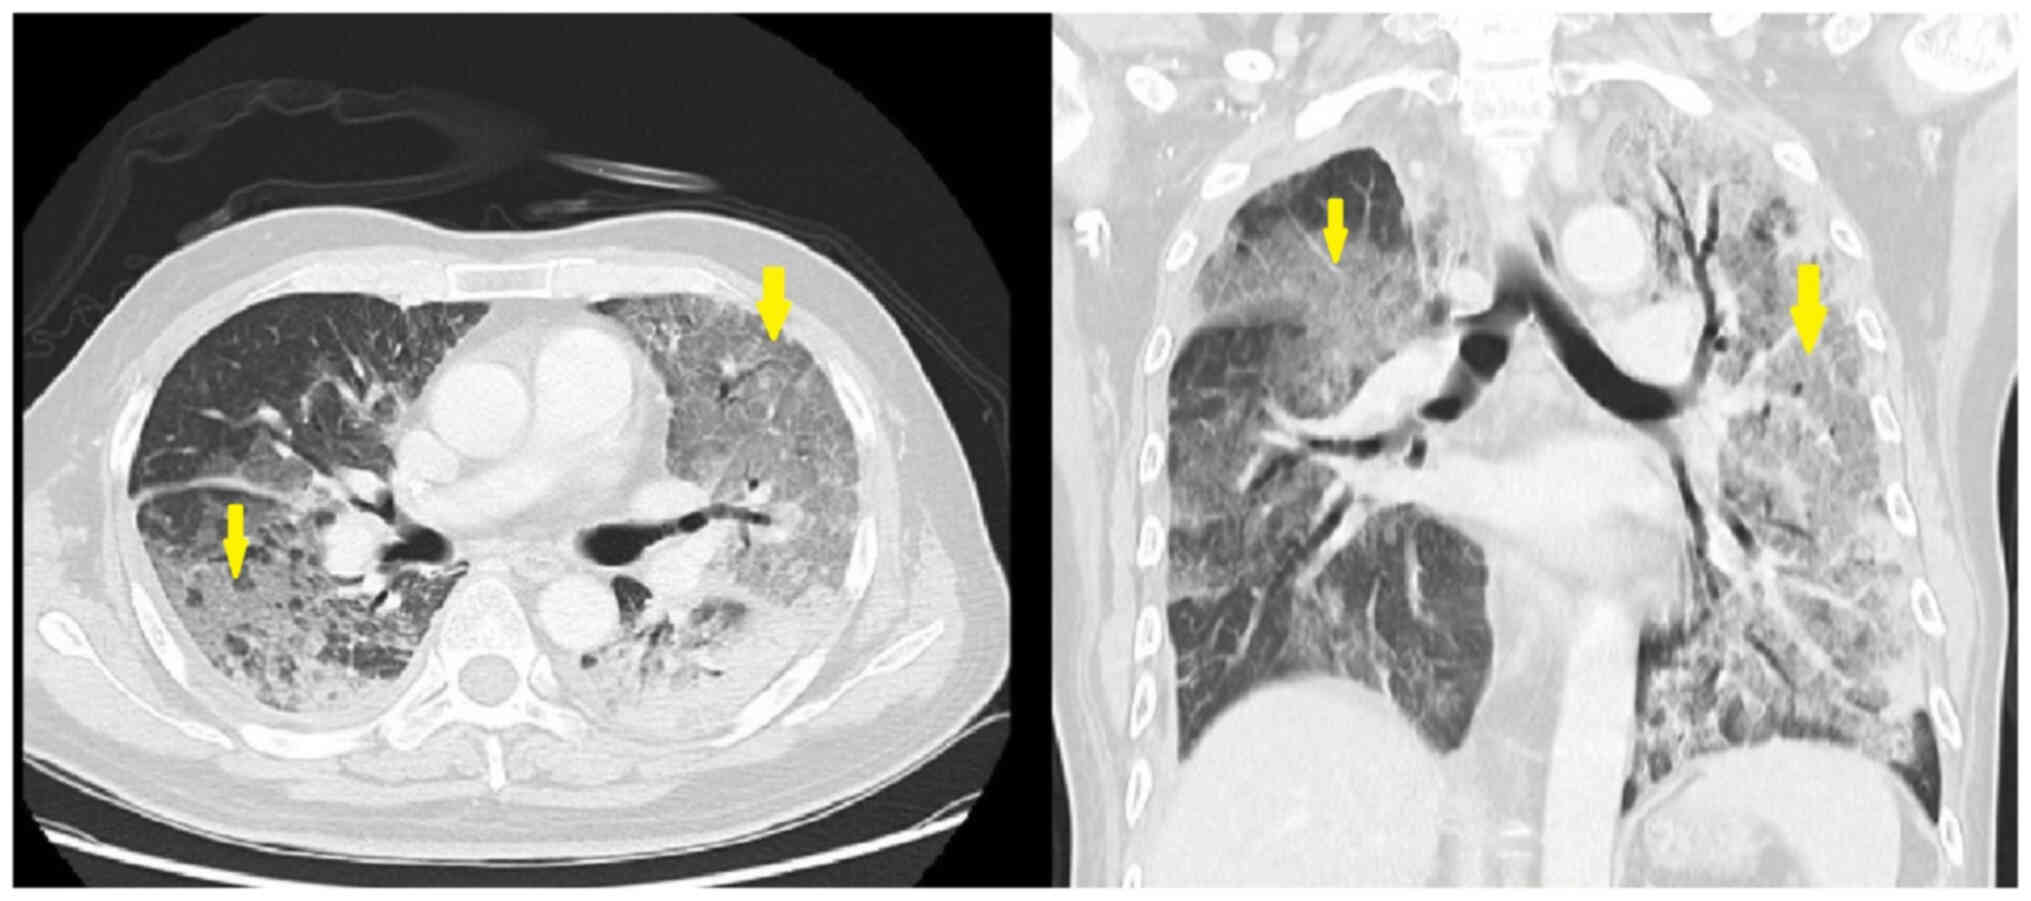

The patient was again admitted to hospital in January 2023 due to progressive dyspnea, and treatment with capmatinib was maintained up to January 2023. A chest X-ray showed bilateral infiltrations. Chest CT scan images showed extensive ground-glass opacity in both lungs and subpleural consolidation, which led to a suspected diagnosis of drug-induced ILD and pneumonia (Fig. 1). The patient was tested for influenza A and B, coronavirus disease 2019, and Legionella and Mycoplasma antibodies, which are potential causes of ILD and were common tests conducted in Taiwan in 2021; however, these tests were negative. Systemic steroids consisting of 120 mg methylprednisolone per day and antibiotics consisting of 750 mg levofloxacin per day were then prescribed and the patient's oxygenation status improved. The follow-up chest X-ray also showed improvement of the bilateral infiltrations. Antibiotics were discontinued and systemic steroids were gradually titrated until the patient was only receiving oral prednisolone. The follow-up chest CT images demonstrated marked regressive changes in the bilateral ground-glass opacity (Fig. 2). The patient was discharged after 14 days of treatment. Treatment with oral tepotinib, another type of MET inhibitor, was provided once daily [administered as two 225 mg tablets (450 mg)] for 21 days at 1 month post-discontinuation of capmatinib treatment. The patient undergoes monthly follow-up chest X-rays, with chest CT scans every 3 months. The last follow-up was in June 2023, and currently, there are no signs of ILD.

Figure 1.

Chest computed tomography images. Extensive ground-glass opacity in both lungs and subpleural consolidation were observed (arrows), which was suspected to be drug-induced interstitial lung disease and pneumonia.